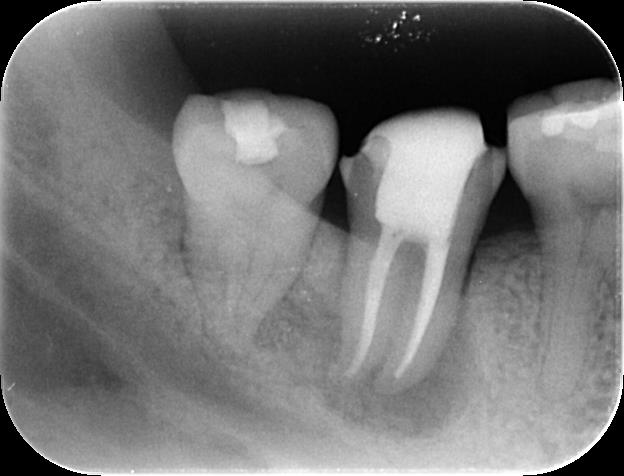

当院では、これらの条件を正確に評価するため、通常のレントゲンに加えて、歯を近心(手前側)と遠心(奥側)の2方向から撮影し、さらに必要に応じて歯科用CT撮影を行います。歯科用CTは、顎の骨や歯の状態を三次元的に把握できるため、レントゲンだけでは分からない病変の広がりや、歯根の形態、破折の有無などを詳細に確認することができます。

各種精密検査の結果、この患者さんの歯は、

● 十分な歯質が残っていること

● 歯根破折は認められないこと

が確認できました。 私たちは、これらの診断結果を患者さんに丁寧にご説明し、「この歯は、適切な手順で治療を行えば保存できる可能性が非常に高いです」とお伝えしました。患者さんの同意を得て、歯内療法の専門医による根管治療を開始することになりました。

治療後の経過をレントゲン写真で追跡したところ、治療開始から3ヶ月後には、根の先にあった黒い影(骨が溶けていた部分)が大幅に縮小し、骨が再生してきている様子が確認できました。そして、半年後には病変は消失し、健康な骨組織に置き換わっていました。